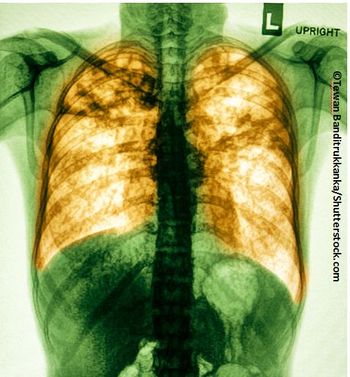

Sometimes called "asthma of the esophagus," EoE requires early detection for optimal management. This 2015 ACG presentation reviews Dx and Rx for primary care.

For a young man with eosinophilic esophagitis, which potential allergen is most likely the cause of his symptoms?